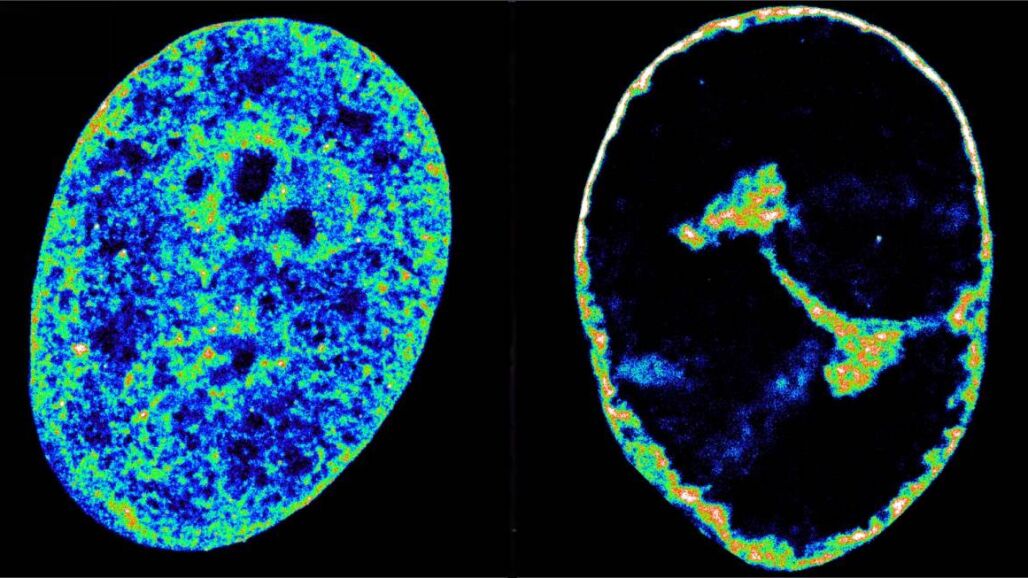

Los hallazgos fueron posibles combinando microscopía de superresolución, una técnica de imagen que puede ver estructuras de 20 nanómetros de ancho (algo aproximadamente 3.500 veces más fino que un cabello), con Hi-C, una técnica que revela qué fragmentos de ADN se están tocando dentro del núcleo. Utilizaron ambas técnicas para entender los mecanismos que usa VHS-1 para secuestrar a las células humanas.

El hurto molecular hace que la transcripción se venga abajo en todo el genoma del huésped, lo que a su vez provoca que la cromatina, el estado natural del genoma humano dentro de las células, se compacte en una cáscara densa de solo el 30% de su volumen original.